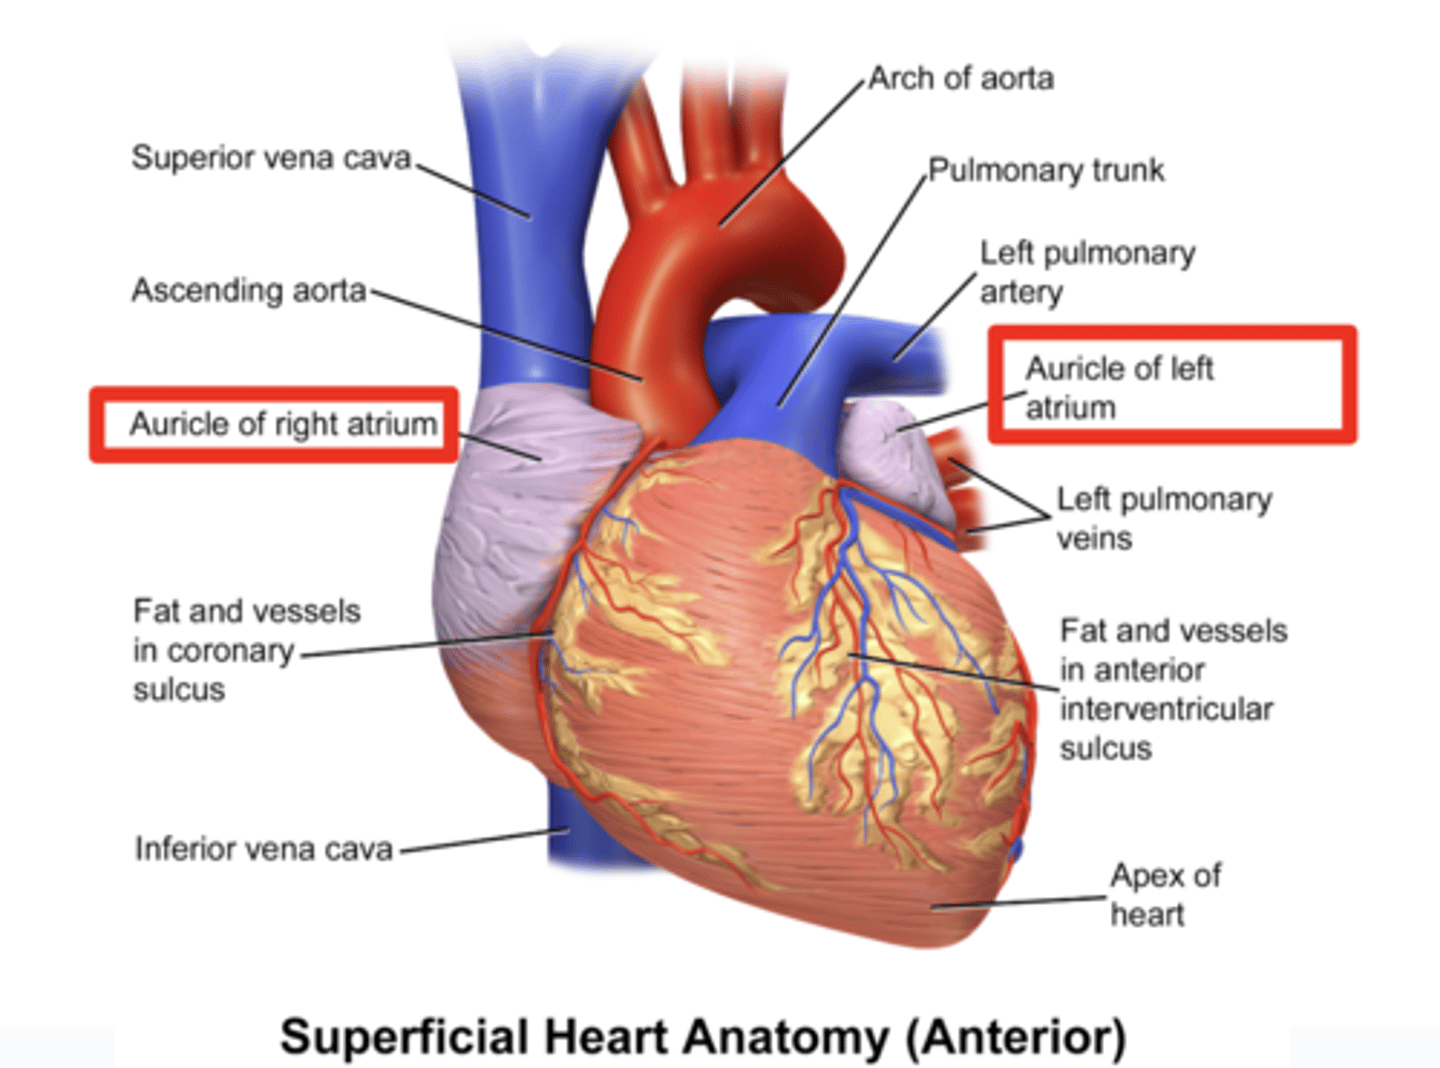

What are the atrial appendages?

Rough trabeculated region of the atria (Extensions of the atria)

External portions of the atria, (Real cavities of the right and left atrium being posterior to these auricles)

ALSO CALLED AURICLES

Describe the location of the main arteries in the anterior view of the heart

The pulmonary trunk exits the right ventricle

. aorta exits the left ventricle.

During early heart development, the pulmonary artery is on the left and the aorta on the right because they develop from a common tube (truncus arteriosus).

What is the pulmonary trunk?

. major blood vessel that plays a crucial role in the circulatory system by carrying deoxygenated blood from the heart to the lungs.

. Divides into left and right pulmonary arteries